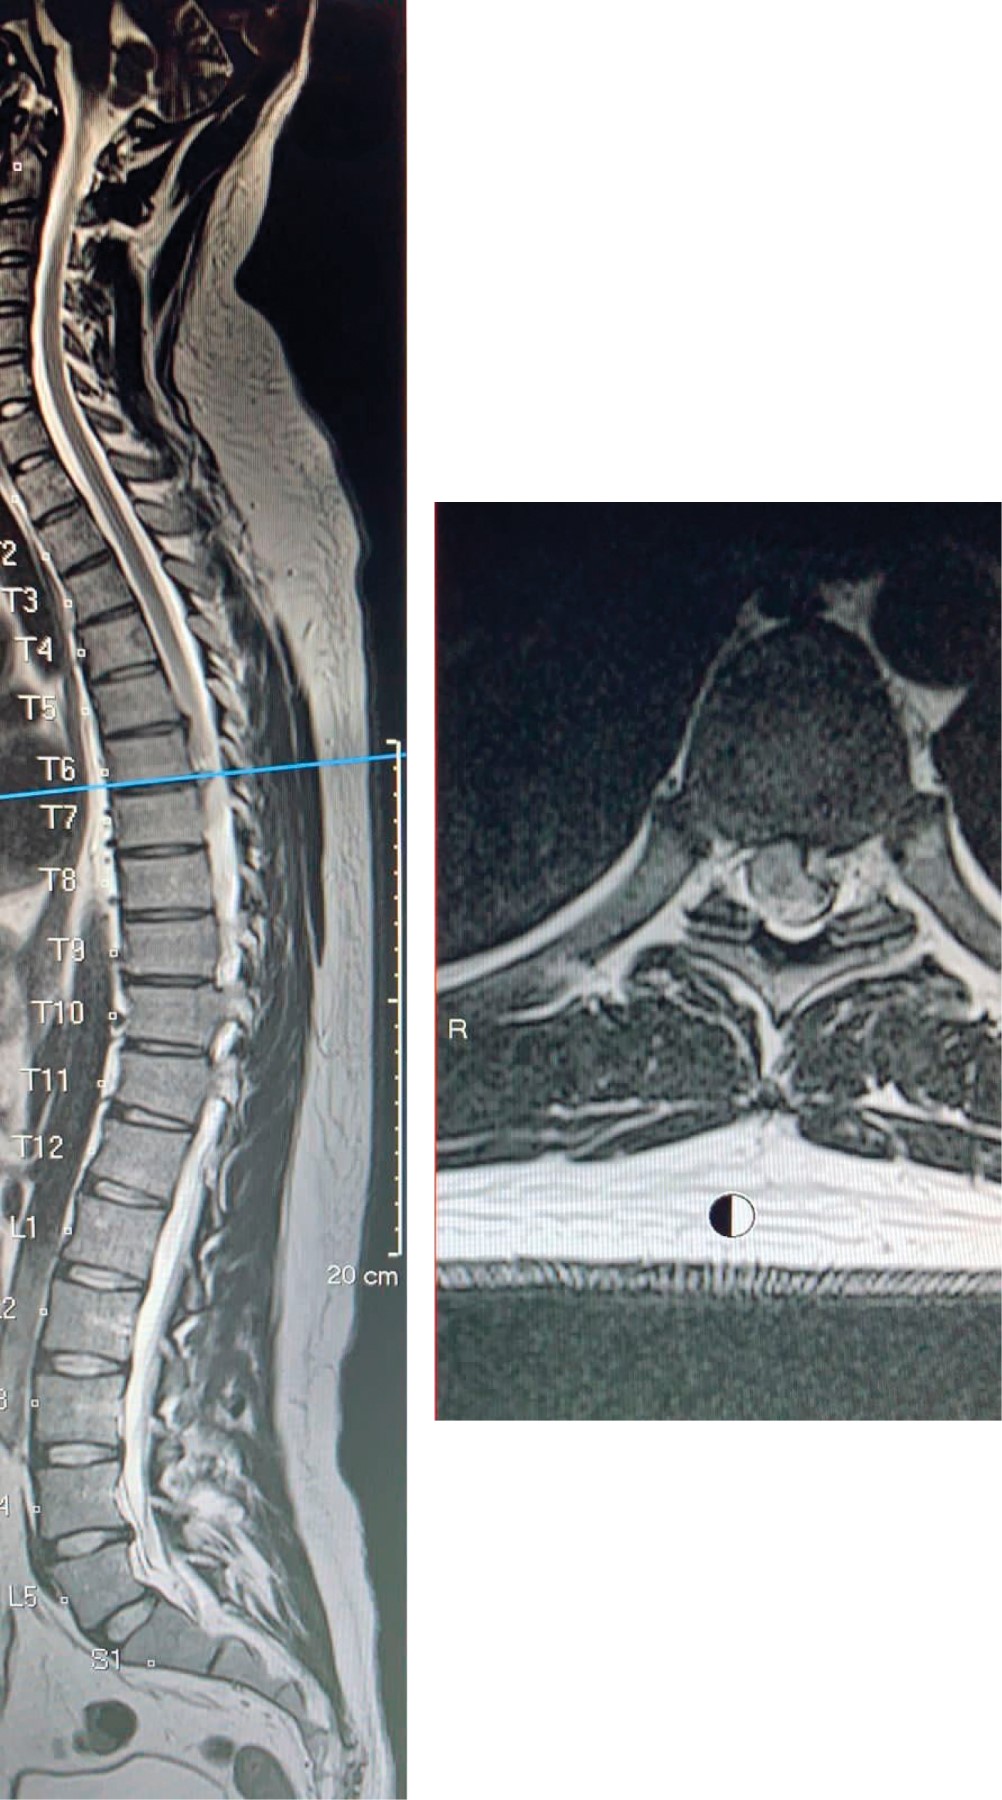

Se realizan estudios de imagen, radiografías y tomografía axial computarizada sin alteraciones, la resonancia magnética simple de columna cervical y torácica con neuroeje en T2 revela hernia discal paracentral izquierda T6-T7, la cual genera compresión medular (Figuras 1 y 2).

Figura 1

Figura 2